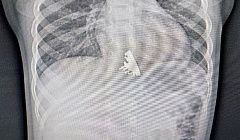

В Иркутске двухлетняя девочка проглотила крейсер «Аврора»

Врачам понадобилось в два раза больше времени для извлечения.